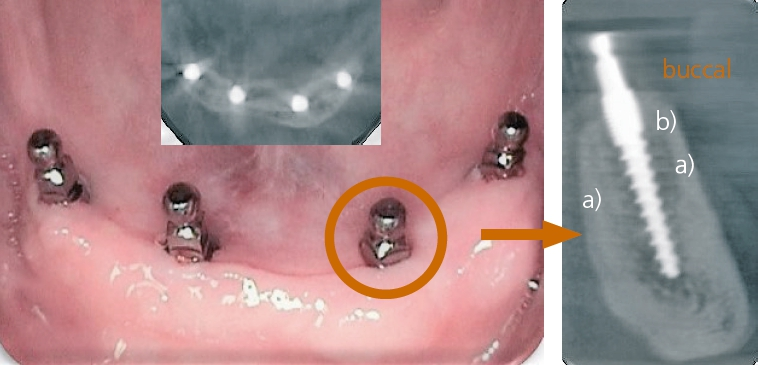

Im Unterkiefer greife ich auf vier einteilige Implantate (mit den Durchmessern 2,5 – 3,0 oder 4,0 mm) mit Kugelköpfen zurück, die jeweils vier Abflachungen der Kugel aufweisen. Deshalb habe ich diese in der Vergangenheit auch als „Tulpen“ bezeichnet. Der Grund für diese Abflachungen sind die O-Ringe der Matrize, die durch die Abflachung nicht schnell „ausleiern“ (durch tägliches Ab- und Wiedereingliedern der Prothese). Eine der abgeflachten Flächen sollte nach bukkal zeigen (siehe orangener Ring Abb. 7).

Man bereitet z.B. mit den bereits seit 2006 zugelassenen, einteiligen Champions Kugelkopf-Implantaten (Länge 8 – 10 – 12 – 14 – 16 mm und Durchmessern 2,5 – 3,0 oder 4,0 mm) immer die komplette Arbeitslänge in mm und addiere i.d.R. sogar 4 mm dazu: Für meine Standardlänge 10 mm bereite ich also mit gelbem und weißem Dreikantbohrer transgingival 14 mm auf, um problemlos und ausreichend tief die Implantate inserieren zu können (Abb. 4-9)!